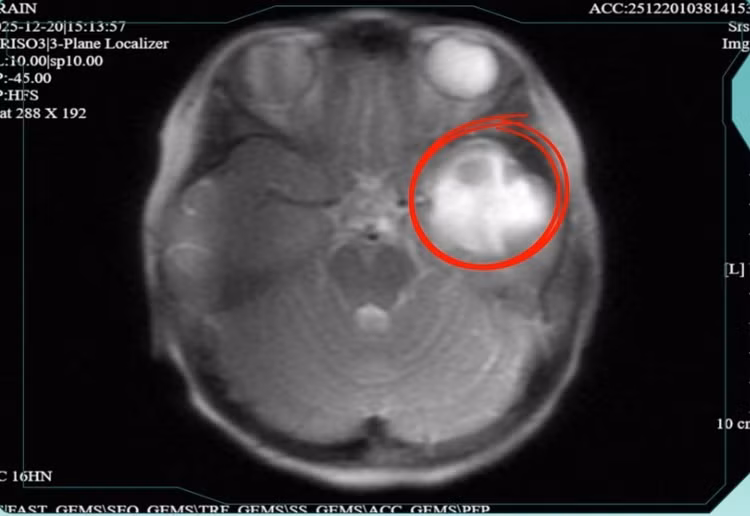

Kết quả chụp MRI sọ não ghi nhận ổ áp xe não tại thùy thái dương trái kích thước 18 × 13 mm, xung quanh là vùng phù não lan rộng, đồng thời có dấu hiệu viêm lan sang màng não lân cận.

Ổ áp-xe não lan rộng - Ảnh BVCC

BSCKI. Phạm Thị Nhường (Khoa Nhi, Bệnh viện Đa khoa Hồng Ngọc cơ sở Yên Ninh), người trực tiếp thăm khám và điều trị cho bệnh nhi cho biết: “Ổ áp xe nằm ở thùy thái dương - vùng não phụ trách xử lý âm thanh, trí nhớ và cảm xúc nên đặc biệt nguy hiểm.

Khi kèm phù não lan rộng gây chèn ép mô não lân cận, người bệnh có nguy cơ rối loạn chức năng thần kinh, co giật, thậm chí vỡ ổ áp xe vào khoang não hoặc lan rộng nhiễm trùng, đe dọa tính mạng nếu không được kiểm soát kịp thời”.